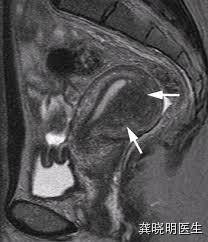

核磁共振检查也会有类似的发现,能够发现肌层有明显的增厚和结构紊乱,在核磁共振上更加明显。

肌腺症在子宫内部若是局部形成一个象肌瘤一样的结节,在超声上可能会比较局限,看起来象是一个肌瘤,但是通常边界不如肌瘤清楚,绝大多数超声认为的腺肌瘤其实都是腺肌症的表现,这在核磁共振检查上更清晰。